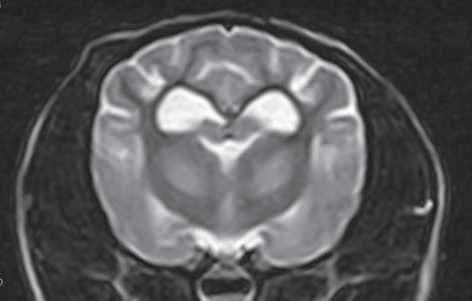

Figura 1. (A y C) Imágenes ponderadas en T2W. (B y D) FLAIR con lesiones hiperintensas en múltiples regiones encefálicas asociados a focos de edema con mayor evidencia en núcleos basales y tálamo (A, B) y lóbulos parietales y temporales (C y D).

A B C D

Figura 2. Imágenes ponderadas en T2W (A, C) y FLAIR (B, D) en las cuales se aprecia una disminución en las lesiones hiperintensas descritas en la figura 1.

Conbasealosresultadosderesonancia magnética (Figura 1), raza y hallazgos neurológicos los pacientes fueron diagnosticados con enfermedad inflamatoria cerebral (Meningoencefalitis de origen desconocido) e iniciaron con una terapia basadaenStee2020,10 conlacombinación decitarabina(Cytosar-U®Pfizer500mg) a dosis de 100/m2 y prednisona a dosis de 1 mg/kg iniciales por 4 semanas (dosis reducción a 36 semanas), para posteriormente evaluar la evolución clínica del paciente y por imagen con las mismas indicaciones de resonancia previamente descritas.

En el presente estudio 5 de 6 pacientes mostraronunamejoracínicasignificativa, enunpaciente(Shih-tzu)elcualingresóen estatus epiléptico no presentó más crisis convulsivas ni se han reportado hasta el momento, el estado mental de los 6 pacientes mejoró de forma significativa, sólounpaciente(Yorkshire)conimágenes por resonancia magnética con herniación subfalcina continuó con giros, los déficits propioceptivos continuaron en 2 de 6 pacientes (Cuadro 3). En las imágenes por resonancia magnética posterior a las 4 semanas iniciado el tratamiento se vio unadisminucióndeledemareportadoque va desde el 85% hasta 50% (Figura 2).